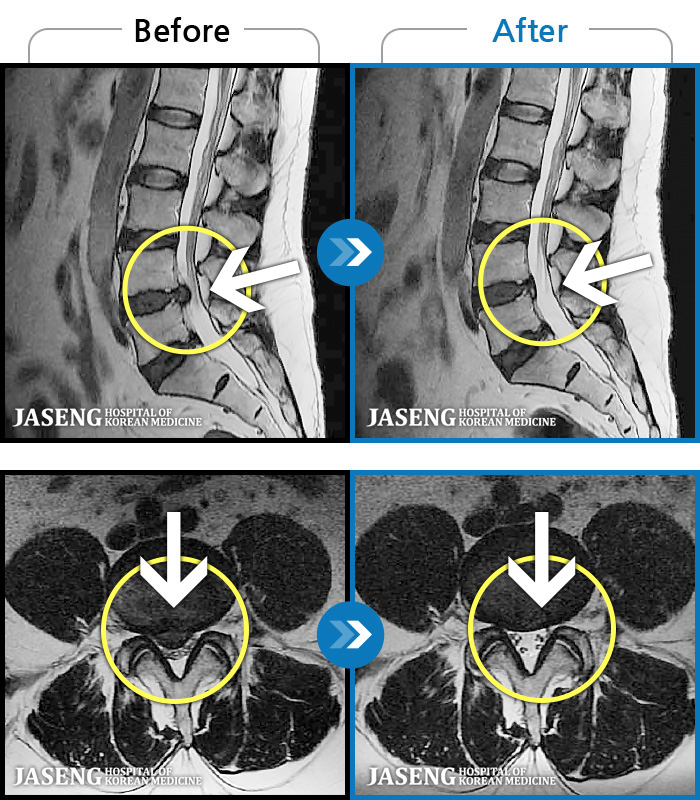

MRI ġ

119 MRI ũ ʸ Ȯϼ.

[Կñ:23.08.01~23.11.18]

[_㸮ũ] 㸮 ٸ ؼ ɰų

No.116

ȸ 733

[Կñ:23.08.21~23.11.20]

[_㸮ũ] 㸮 ϰ ٸ 㸮 ȹٷ .

No.115

ȸ 688